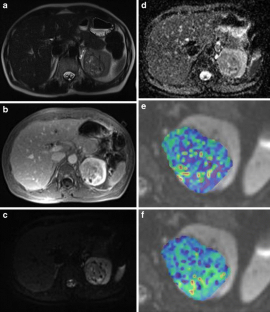

Fig. 1